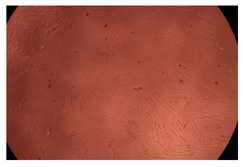

2.4. In Vitro Cytotoxicity Analysis

| Control |  |  | |